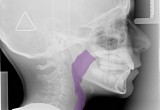

"We ask ourselves if our children are getting enough sleep but the real question should be how well does your Child Sleep," said Leslie Stevens, CEO. "Quality of sleep can be impacted by lack of oxygen caused by a compromised airway, a mouth breather, and a narrow palate."

The Healthy Start system is a non-invasive, non-pharmaceutical treatment that addresses the root cause of children with breathing disorders.  Understanding and even monitoring your child’s sleep patterns have never been more essential.  Many of us do not even realize how much our children struggle to gain the necessary oxygen needed for optimal sleep.

Over the last 20 years, information on adult Sleep Apnea has been widespread.  Adult treatments span many forms by providing band-aids to stop snoring on a night-to-night basis.   Our children are growing and developing and now is the opportunity to provide the proper jaw growth, develop the dentition the way nature intended, correct improper habits, and encourage nasal breathing at night for a lifetime of health and beautiful smiles.

The Healthy Start systems consists of easy to wear oral appliances, worn in a series to address sleep and breathing disorders and straighten your child’s teeth without braces at the same time.